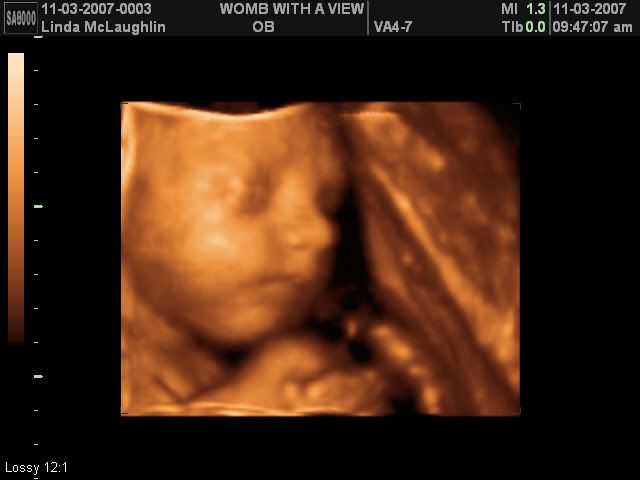

I guess the first thing to start off with is my surprise for M&M a few weeks ago. I got them a 3-d ultrasound session! It was so much fun! We have confirmed she is 100% girl :-) Unfortunately, Miss Baby M wanted nothing to do with picture taking that day so the ultrasound tech had to keep jiggling my belly to get her to turn around - haha!

Anyway, here's a few pictures of M&M's beautiful baby girl <3

Isn't she beautiful? I can't wait to see her in person to see how much she looks like the pictures. <3